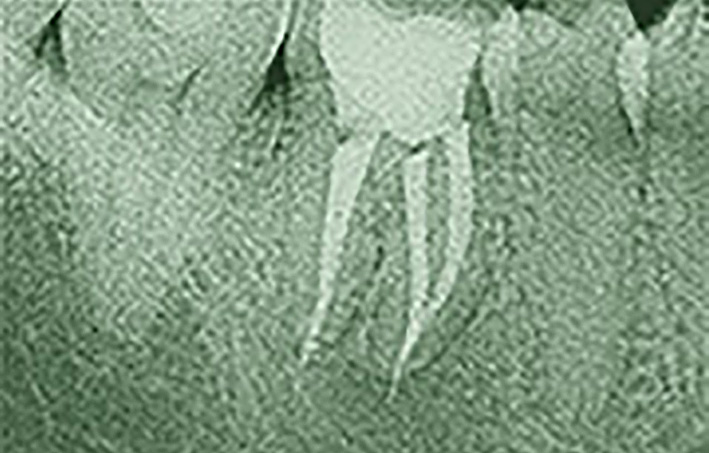

L’Endodonzia è la scienza medica, nell’ambito dell’Odontoiatria, che ha per oggetto i tessuti interni del dente, le patologie e i trattamenti